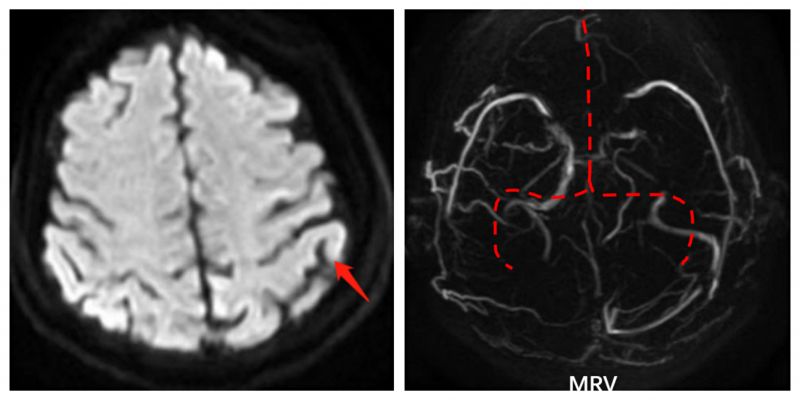

手术前核磁共振检查结果:左图显示左侧顶叶急性脑梗死;右图显示颅内静脉未见显影(矢状窦、横窦、乙状窦)。

在孙殿敬主任医师带领下,神经介入团队立即为患者行血管内治疗。脑血管造影检查证实核磁共振检查结果后,立即经股静脉逆行造影进行静脉窦血栓血管内再通治疗。经过多次支架取栓、导管抽吸,取出大量血栓,同时发现乙状窦狭窄给予球囊扩张治疗。经过5个多小时的艰苦工作,X线曝光时间约1小时,最后造影显示:上下矢状窦、横窦、乙状窦再通,颈内静脉回流通畅。术后继续给予抗凝、脱水降颅压、脑保护以及康复功能训练等治疗,经北院神经内一科全体医护人员悉心治疗与护理,患者病情逐渐好转,目前已康复出院。